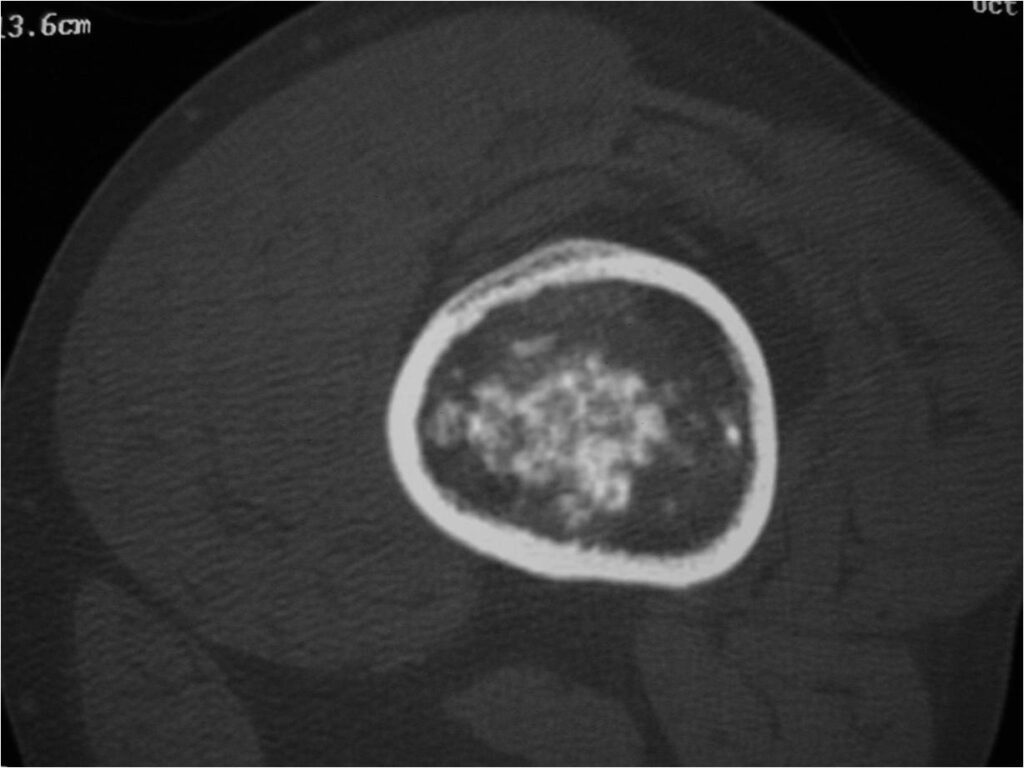

- MRI

- Lobulated margin

- Marked increased intensity long TR images

- Calcified chondroid – low intensity all sequences

MRI:

- Lobulated margin (Lobular Growth Pattern)

- T1 Weighted Images: Intermediate Signal Intensity

- Calcifications will be low signal

- T2 Weighted Images: High Signal Intensity

- High water content shows as high signal on T2 weighted images

- There should never be any cortical destruction nor a soft tissue component. If this exists then the tumor must be a chondrosarcoma.

- Endosteal scalloping and cortical expansion is acceptable for phalangeal tumors. In most benign long bone cartilage tumors there is minimal endosteal scalloping but there should be no cortical expansion nor thickening. There should be no cortical destruction and no soft tissue component associated with an enchondroma. Cortical destruction, periosteal thickening, cortical expansion and a soft tissue component indicates a chondrosarcoma of the long bone.

- Endosteal erosion>2/3 cortical thickness on a CT scan